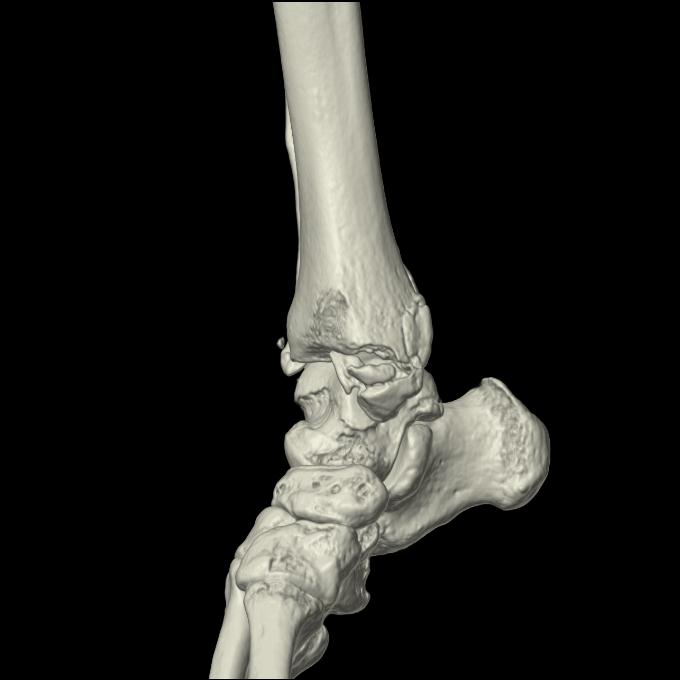

102755 1/4 2R 1/15 2R 右足関節 68歳女性 右三果脱臼骨折